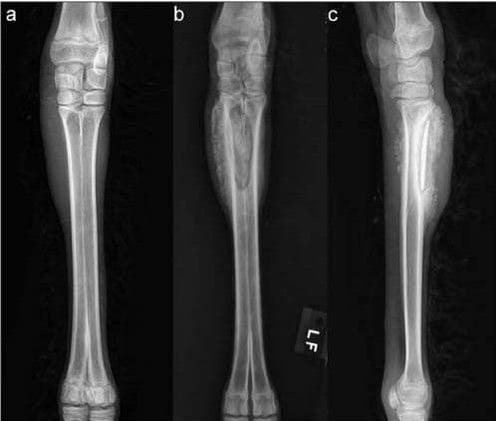

MusculoskeletalMusculoskeletal